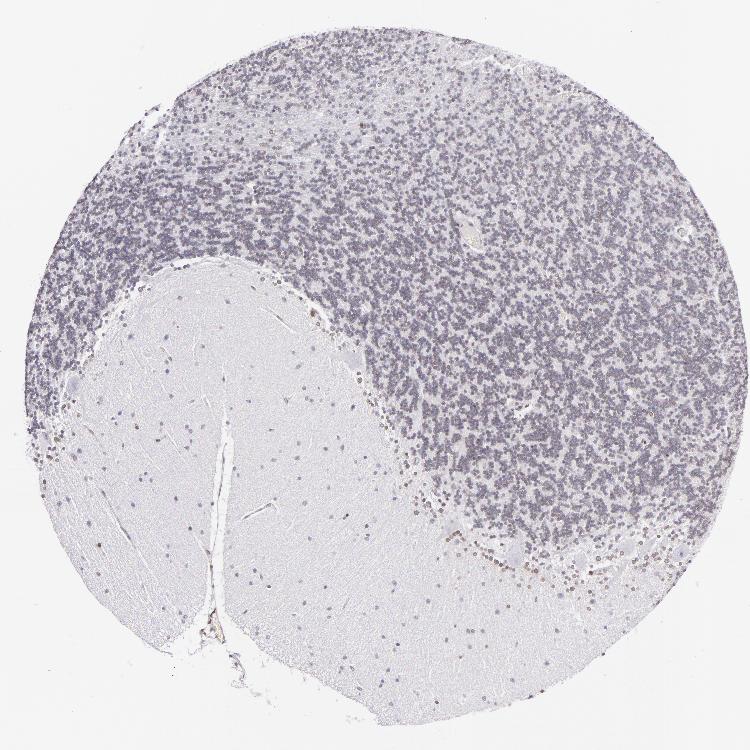

CEREBELLUM - Antibody stainingi

Antibody staining in the annotated cell types in the current human tissue is reported as not detected, low, medium, or high, based on conventional immunohistochemistry profiling in selected tissues. This score is based on the combination of the staining intensity and fraction of stained cells.

Each image is clickable and will lead to virtual microscopy that enables deeper exploration of all samples and also displays staining intensity scores, fraction scores and subcellular localization as well as patient and tissue information for each sample.

Antibody HPA000609Antibody CAB001545Antibody CAB002029Antibody CAB062552

Purkinje cells Not detectedNot detectedNot detectedNot detected

Cells in granular layer Not detectedNot detectedNot detectedNot detected

Cells in molecular layer Not detectedNot detectedLowNot detected